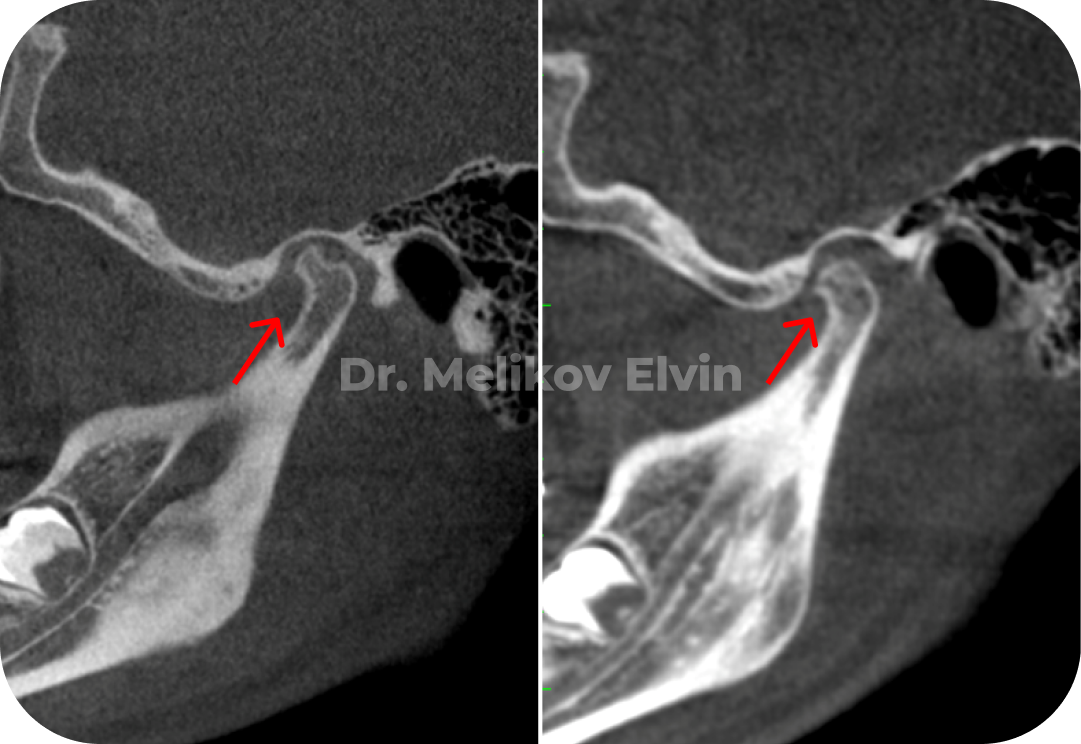

Магнитно-резонансная томография ДО.

Заключение.